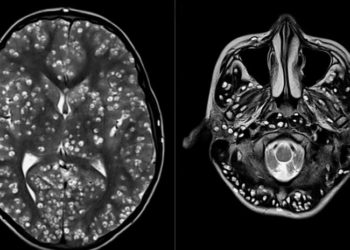

Un hombre que se quejaba de constantes dolores de cabeza y que sufría convulsiones fue informado por médicos de que ...

Médicos indios descubrieron el cerebro de un joven de 18 años plagado de quistes causados por un parásito porcino. El ...